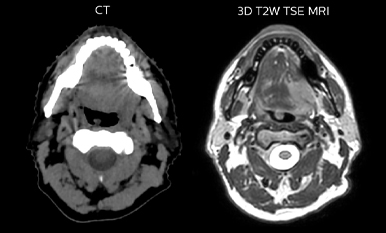

Epidermoid carcinoma of the left tongue base

The patient was diagnosed with an epidermoid carcinoma of the base of the left invading the amygdala lodge and the amygdaloglossal groove. Radiochemotherapy with curative aim was prescribed with a dose of 70 Gy for the tumor, 66 Gy on the suspicious nodes and 56 Gy on the elective drainage areas - in 33 fractions.

T2W 3D, 3D STIR and mDIXON MRI scans.

Comparison of CT simulation scan (left) and T2W 3D MRI (right)